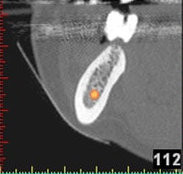

Auf Basis einer computertomografischen (CT-) Kieferaufnahme ist eine dreidimensionale Darstellung der Knochen möglich. Der Zahnarzt kann dann am Computerbildschirm die Knochenqualität (z. B. Knochendichte) beurteilen und die optimale Position der Implantate im Vorfeld planen. Durch Verwendung spezieller Röntgenschablonen lässt sich auch die erwünschte Zahnstellung in die Planung einbeziehen. Die Simulation der OP erlaubt, das zu erwartende Ergebnis mit größtmöglicher Sicherheit vorherzusagen und dem Patienten am Bildschirm zu veranschaulichen.

(siehe Bild 3 und 4).